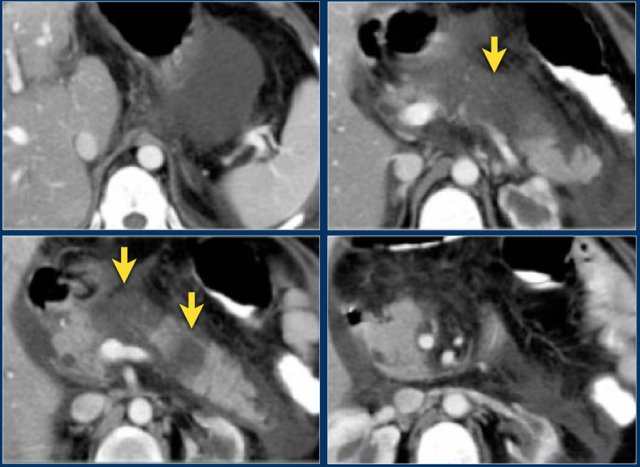

The CT shows an acute necrotizing pancreatitis.

The body and tail of the pancreas do not enhance.

There is normal enhancement of the pancreatic head (arrow).

More than 50% of the pancreas is necrotic and there are at least two collections.

CTSI: 4 + 6 = 10 points.